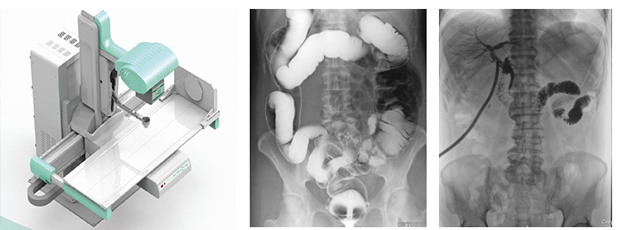

动态DR的出现,将影像诊断带入了便捷准确的新阶段。动态DR能在透视的情况下观察病灶,实时点片,完全避免了传统DR盲拍的局限,提高诊断效果与效率,从而完全满足患者的诊断要求。那么如何判断真正的动态DR?

动态DR是一款多功能DR,能够数字拍片、数字透视、数字造影。

动态DR具有大幅面(17inch×17inch)高清拍片、大幅面(17inch×17inch)透视、视频实时保存回放、可视化造影、毫秒级点片等基础功能,以及断层融合、数字减影等延展性功能。

普爱医疗作为全球较好的数字影像设备供应商,专注于DR系列产品的技术创新,在全国范围内率先推出动态DR。以其“一机多用”集常规拍片、胃肠、透视、造影于一体的多功能作用深受放射科临床医生的钟意。